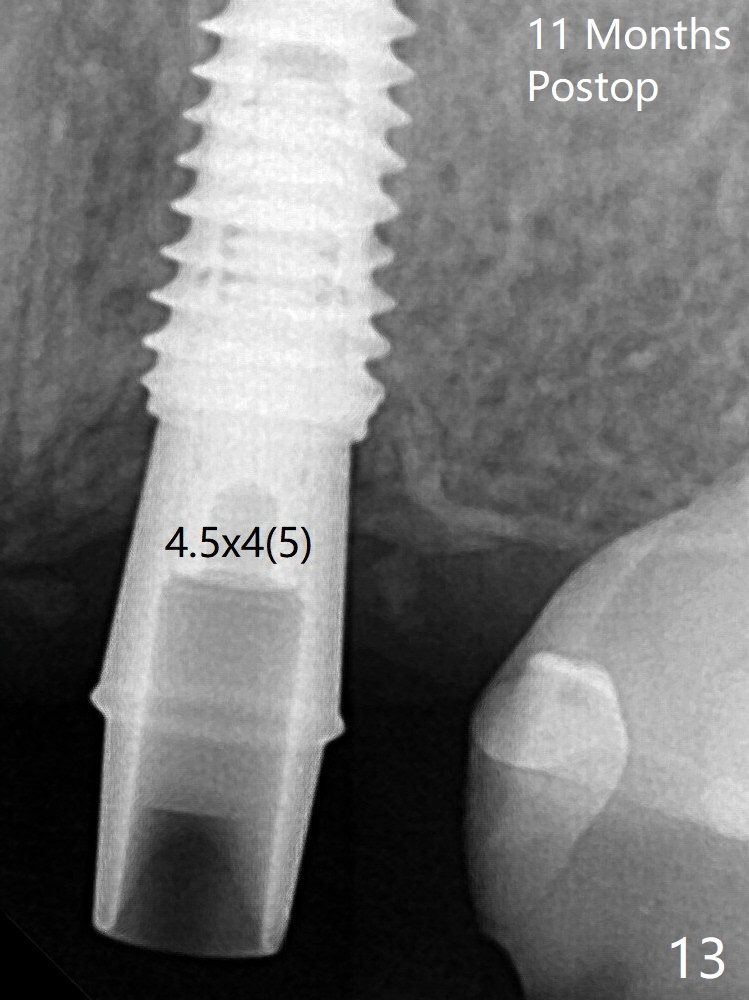

There is crestal remodeling without implant thread exposure 11 months postop (Fig.13).